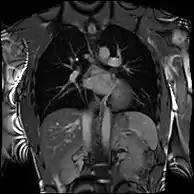

Atrial septal defect with dilation of the right ventricle by CMR

Partial Anomalous Pulmonary Venous Drainage by CMR